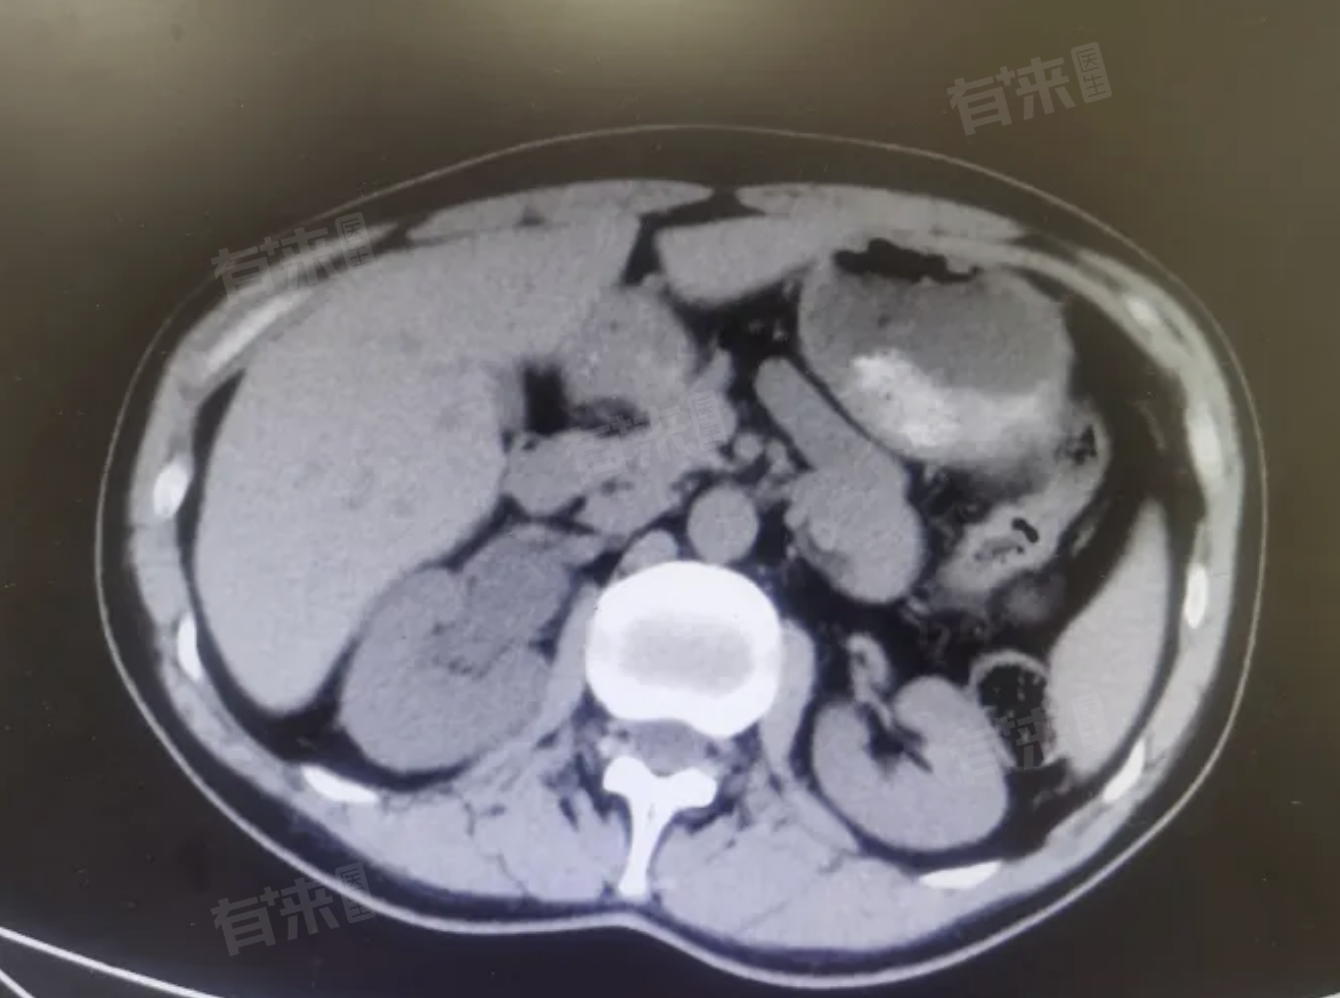

到医院后,医生给安排做了上腹部CT 检查,结果发现右侧输尿管上部有一枚大约4 - 5mm 的结石,还伴有右肾轻度积水。

血常规检查倒是没发现明显异常。结合这些症状和检查结果,医生诊断他得了输尿管结石。